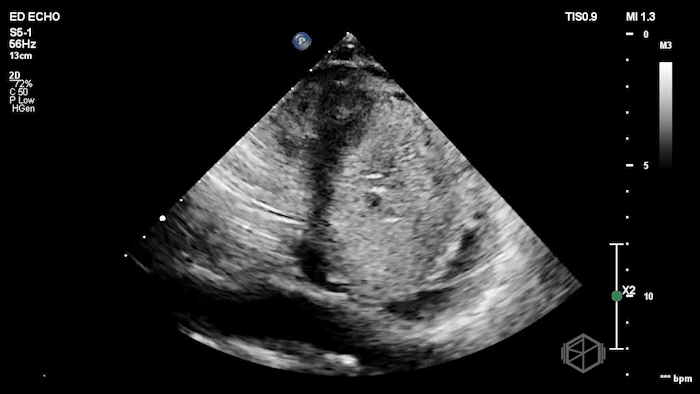

Their Cardiac POCUS showed:

POCUS showed marked left ventricular wall thickening, a dilated right ventricle, biatrial enlargement, a small LV cavity, and a small pericardial effusion. The left ventricular myocardium also had a mildly granular or β€œspeckled” appearance.

Diagnosis: Findings concerning for infiltrative cardiomyopathy (cardiac amyloidosis)